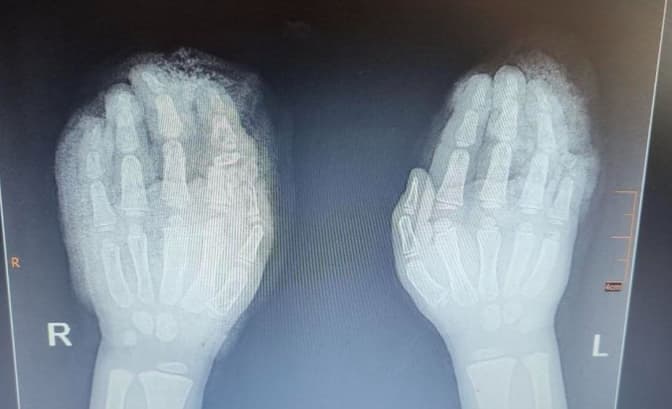

П’ятирічний хлопчик із Львівщини отримав складні травми обох рук під час сільськогосподарських робіт. Дитина спершу втрапила однією рукою в січкарню, а намагаючись витягнути її — сильно пошкодила й іншу кінцівку. Його терміново доставили до лікарні. Про це повідомляє Центр дитячої медицини. Лікарня «Охматдит».

За словами медиків, при поступленні у дитини діагностували:

- множинні рвано-скальповані рани та дефекти шкіри на обох кистях,

- відкриті переломи кількох пальців,

- часткову втрату м’яких тканин і частин пальців.

«Лікарі буквально «збирали» пальці дитини по частинах, уламки пальців були зафіксовані за допомогою спиць. Згодом, коли все зрослось, спиці видалили», — йдеться у повідомленні.

Через втрату шкіри на одному з пальців була проведена ще одна операція - пластика шкіри, взятої з передньої поверхні стегна. Для цього з передньої частини стегна взяли тонкий шар шкіри за допомогою дерматома — спеціального медичного апарата, що дозволяє точно отримати матеріал для трансплантації.

Після хірургічних втручань хлопчик пройшов курс реабілітації: фахівці працювали над розробкою рухів у суглобах кистей і пальців. Завдяки професійній роботі медиків вдалося зберегти функціональність обох рук.